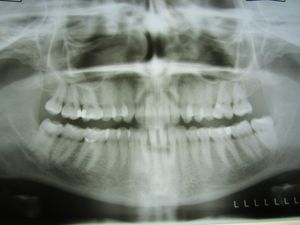

Zahnfüllungen im Röntgen: Haltbarkeit als Problem (Foto: Liza Litsch/pixelio.de) |

Portland (pte026/05.03.2019/11:30) Forscher der OHSU School of Dentistry http://bit.ly/2NMsWKw haben ein neues Material für Zahnfüllungen entwickelt, das gegenüber bisherigen Produkten doppelt so widerstandsfähig gegen Bruch ist. Dabei kommt als Zusatz Thiourethan zum Einsatz, das auch für die Schutzbeschichtung von Autos oder Terrassen verwendet wird. Zusätzlich wurde ein Kleber entwickelt, der nach sechs Monaten Einsatz haltbarer ist als jener, der derzeit oft eingesetzt wird. Gemeinsam sollen sie für eine größere Haltbarkeit sorgen.